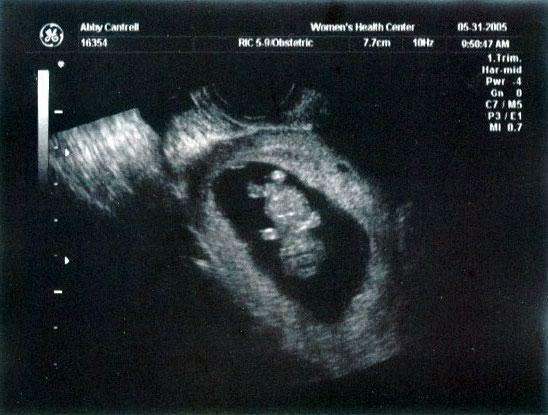

10 week ultrasound ~ There's a BABY in there!